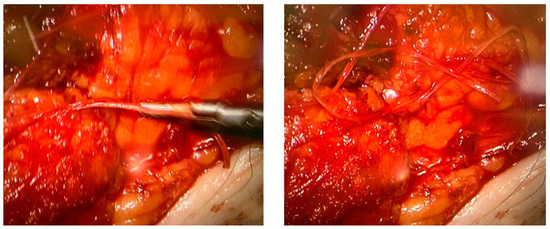

NCMRL protocols are still evolving, but the base of this examination consists of heavily T2-weighted sequences, with very long both Repetition Time (TR) and Echo Time (TE), usually performing 3D sequences (to create rotating 360° 3D post-processed images and maximum intensity projection (MIP) reconstructions), with very long TR/TE ratio to assess the extent and distribution of the lymphedema [34] (Figure 1).

Figure 1. Two different NCMRL. On the left (a), a patient with mild post-prostatectomy lymphedema with a left iliac lymphocele associated. On the right (b), mild–severe lymphedema is more represented in the left limb, with scrotal localization.